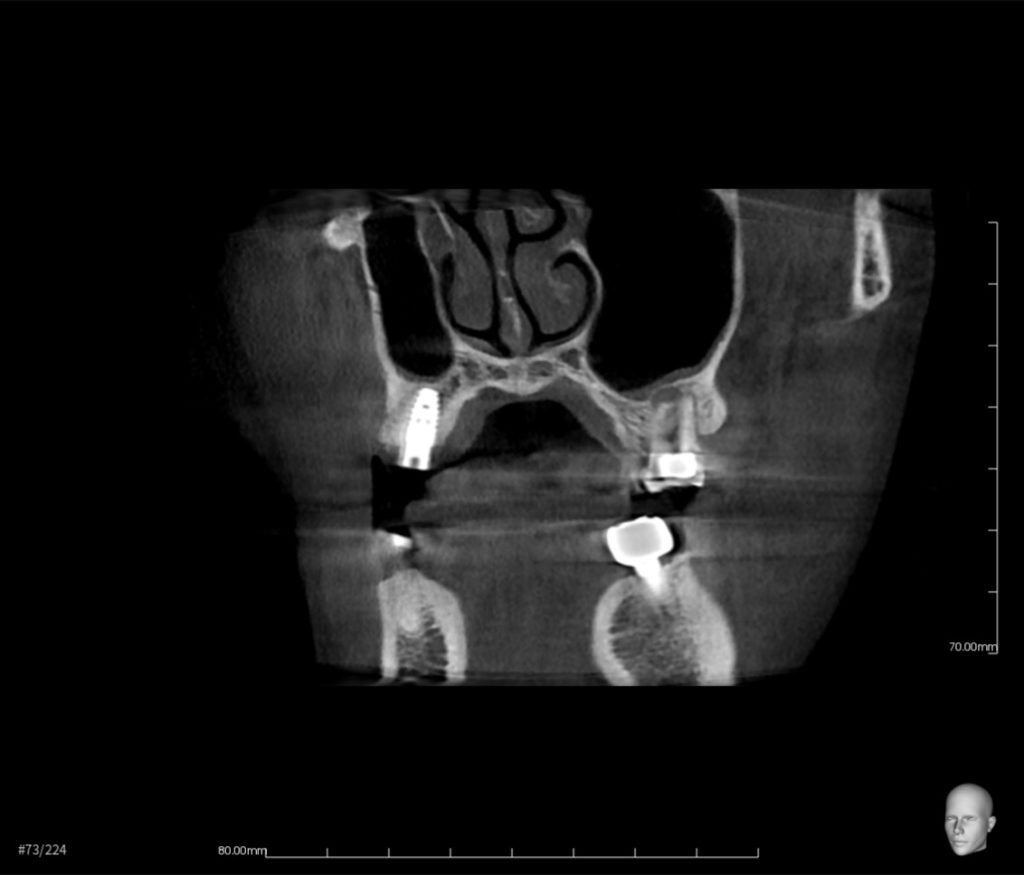

抜歯と同時にインプラントを埋入し、3ヶ月後に被せ物をセットできると思います。

抜歯即時インプラント治療の費用 約58万円(税抜)